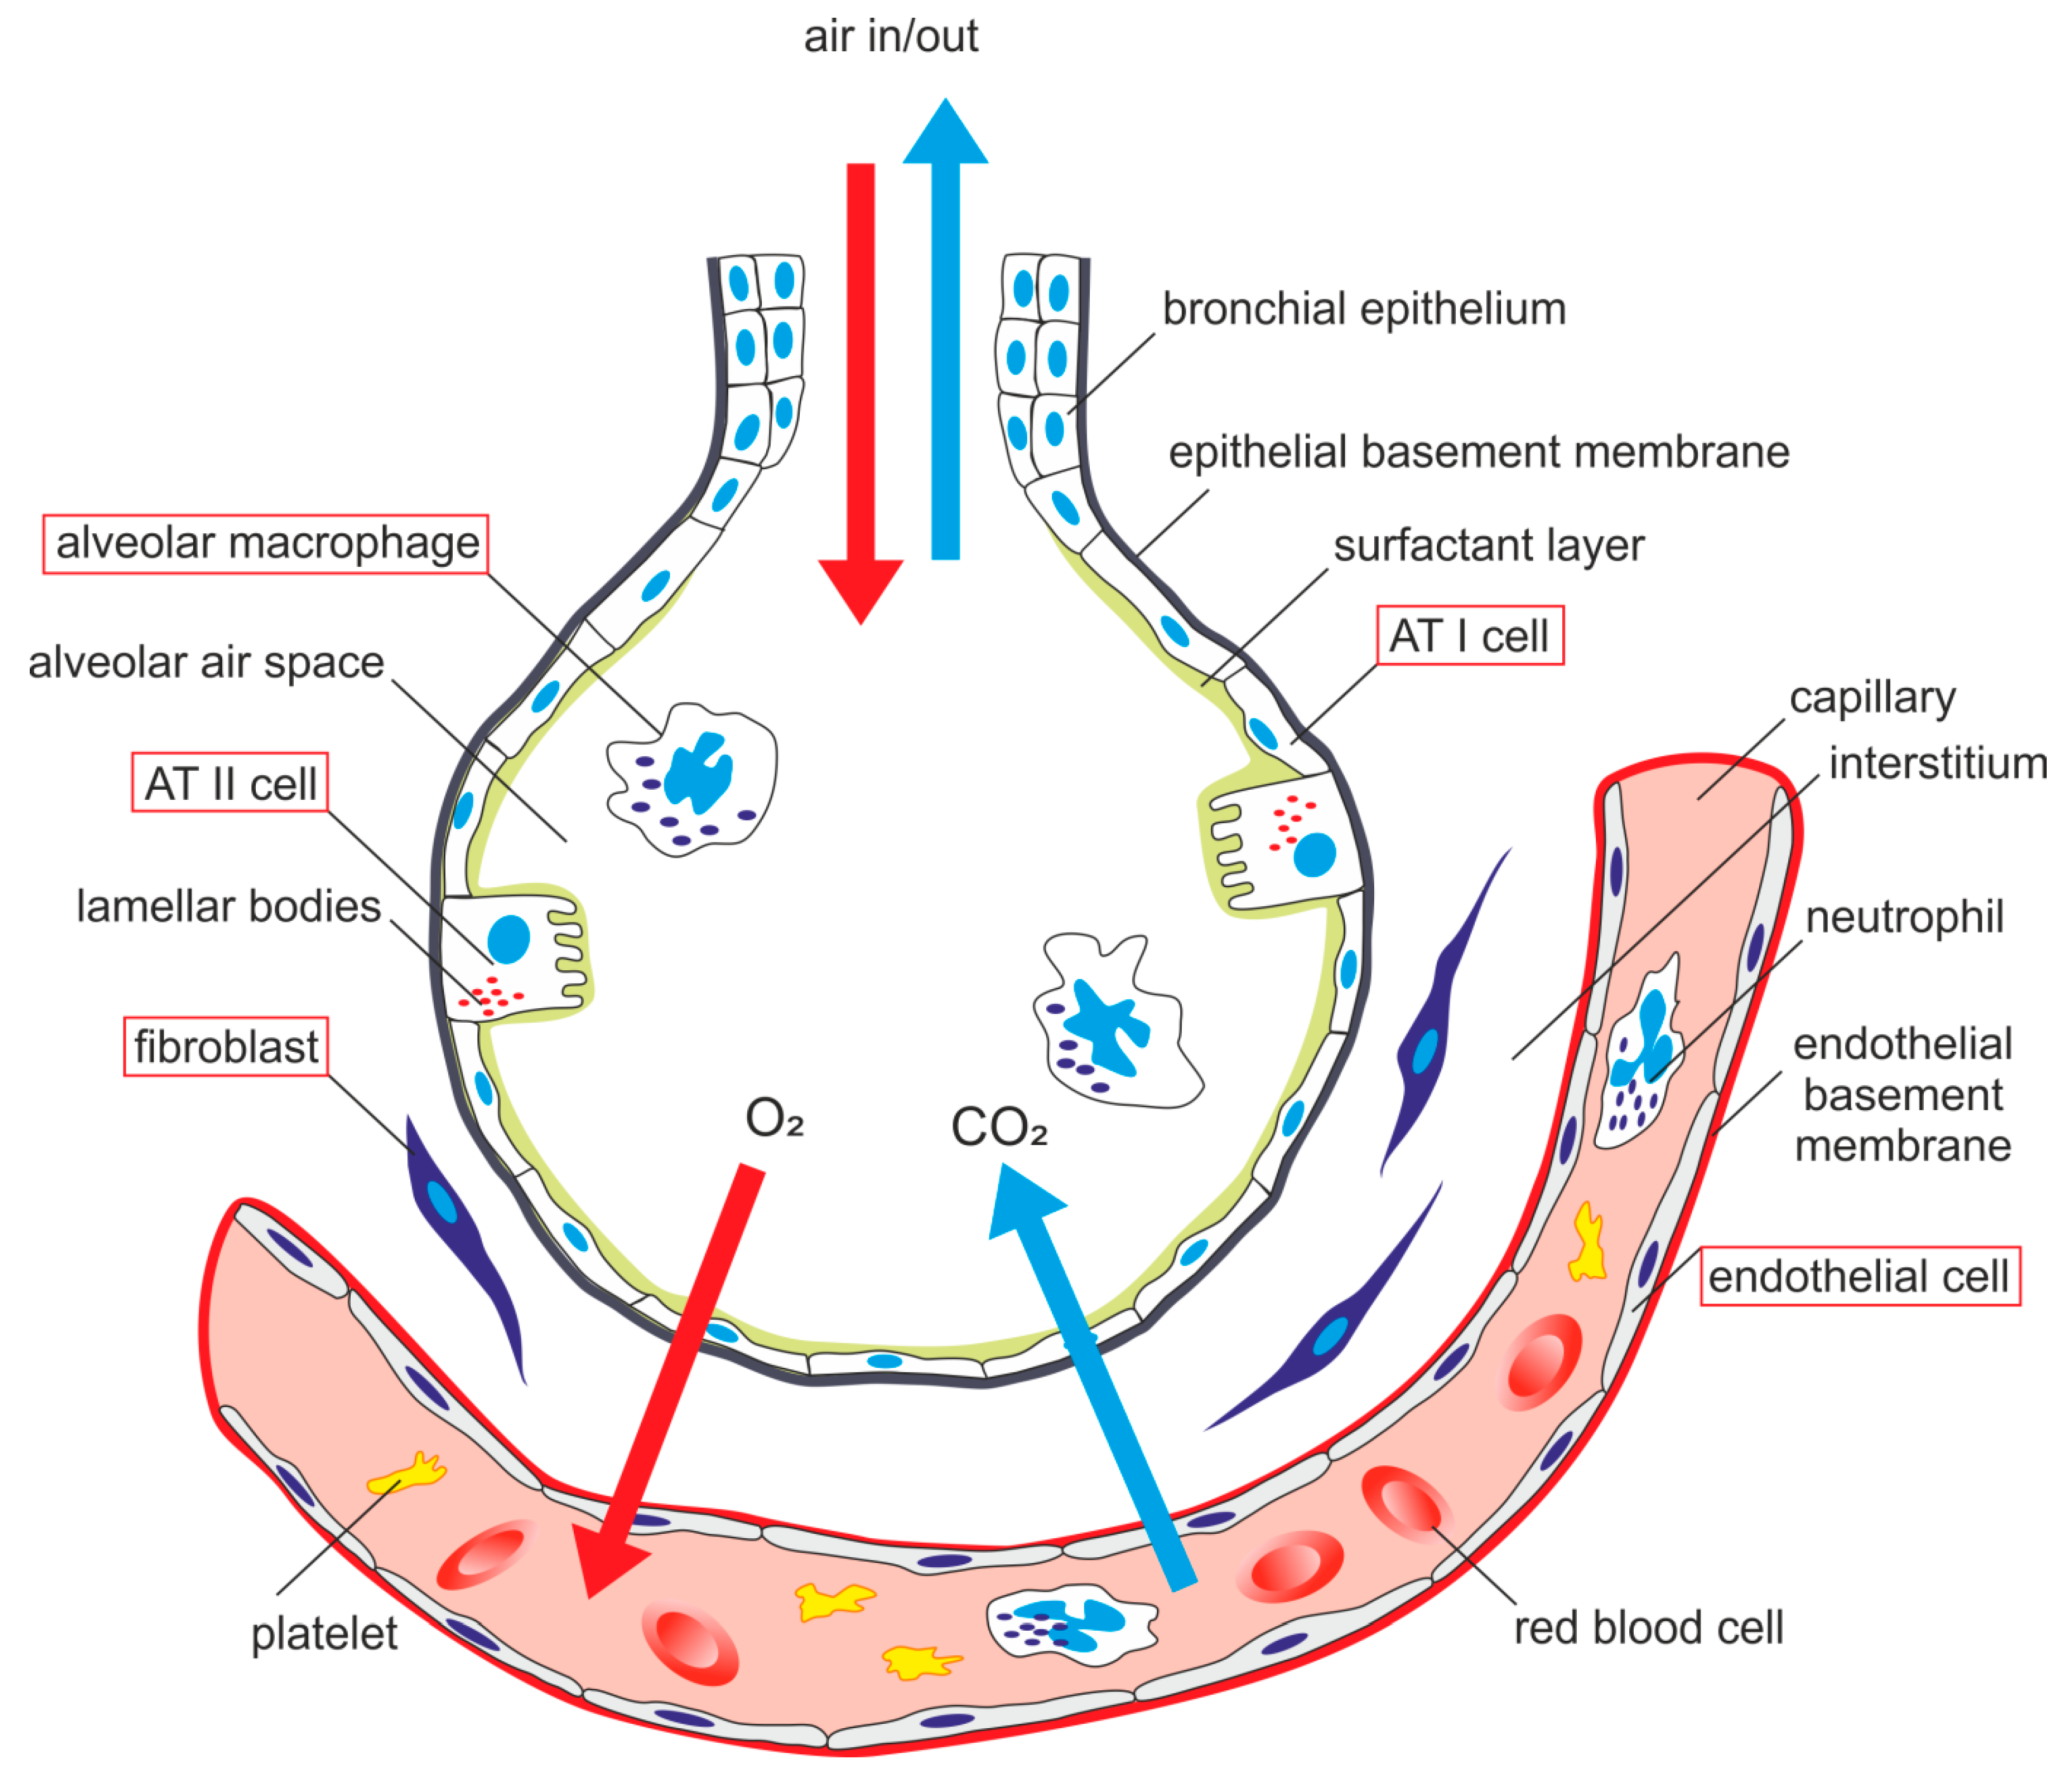

IJMS | Free Full-Text | Alveolar-Capillary Membrane-Related Pulmonary

www.mdpi.com

www.mdpi.com

alveolar capillary membrane pulmonary lung cells injury schematic acute cell epithelial type ii related